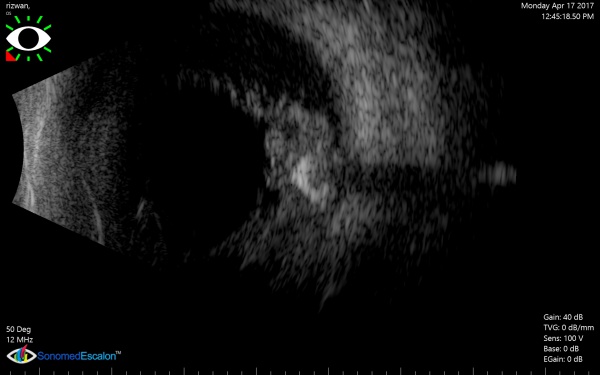

[The funnel RD is attached to the disc and is not showing after-movements with ocular movements.]

In cases of bullous retinal detachments with 'shifting fluid' (in sitting position the RD is inferior bullous and superior retina seems attached; in supine position, there is a total retinal detachment), it may be necessary to rule out an exudative retinal detachment (ERD). ERD usually shows subretinal echoe. A choroidal mass may be detectable, or the ultrasound may reveal another cause of the ERD (e.g., posterior scleritis, Vogt-Koyanagi-Harada syndrome).

A case of choroidal hemangioma[6] with exudative RD. Note the limited after-movements.